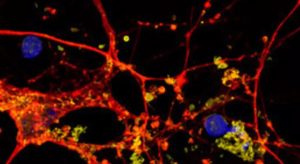

Un team di ricerca del CNR-Isasi di Napoli e del TIGEM di Pozzuoli ha realizzato un progresso straordinario nel campo della biologia cellulare. Hanno sviluppato una nuova tecnica che consente di osservare i lisosomi in tre dimensioni all’interno di cellule vive, senza ricorrere a marcatori fluorescenti. Questo approccio innovativo rappresenta un passo avanti significativo nella comprensione dei lisosomi, organelli cruciali per il metabolismo cellulare e interessati in oltre 60 malattie genetiche rare, note come malattie da accumulo lisosomiale (LSD), che colpiscono principalmente il sistema nervoso centrale.

Grazie all’innovativa tecnologia della tomografia olografica in configurazione citometrica a flusso (HTFC), i ricercatori hanno potuto misurare diversi parametri biofisici dei lisosomi, come densità e volume. Hanno scoperto, ad esempio, come l’accumulo di varie molecole possa alterare le proprietà fisiche dei lisosomi, consentendo di differenziare le cellule sane da quelle affette da NPC1. Questa innovazione apre nuove strade per monitorare gli effetti di terapie farmacologiche e genetiche, nonché per identificare biomarcatori nuovi e specifici per le malattie da accumulo lisosomiale.